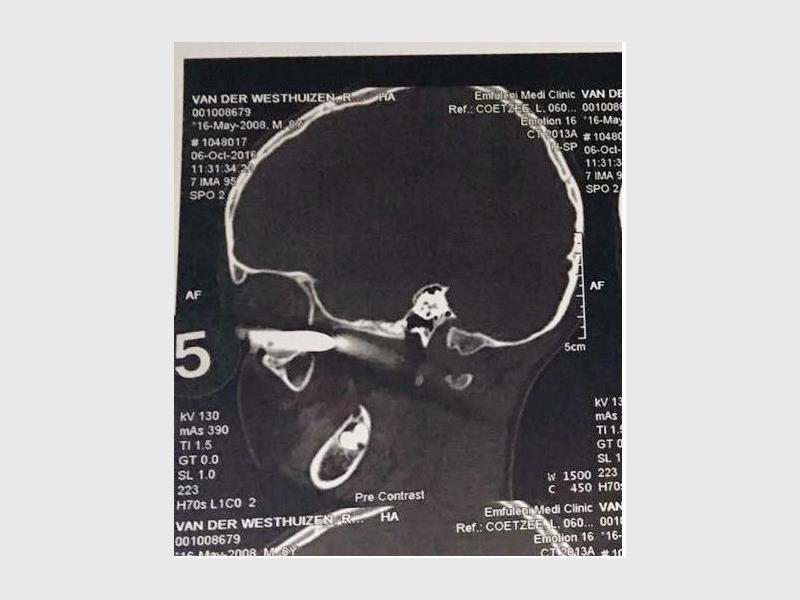

Sy en haar swaer, ’n oogkundige, is dadelik met Ryno na Cormed-kliniek, van waar hulle vir ’n dringende CT-skandering na Mediclinic Emfuleni verwys is. Jonet het vertel dat die metaalstafie haar seun se breinkas met enkele millimeters gemis het.

Dit was die eerste keer ooit dat hulle so ’n besering gesien het. Hulle kon vasstel dat Ryno se oog normaal reageer ondanks die metaalstaaf wat dit byna heeltemal van binne af toegedruk het, maar hulle kon nog nie bepaal wat die skade aan omliggende senuwees, bloedvate en die oogkas was nie.